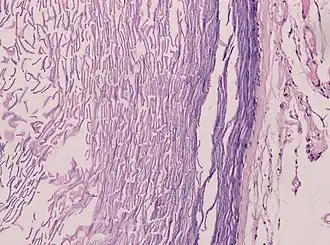

Histopathologie, montrant un épithélium pavimenteux stratifié kératinisant et une lumière contenant des débris de kératine

Histopathologie montrant l'épithélium et la kératine lamellaire (à gauche)